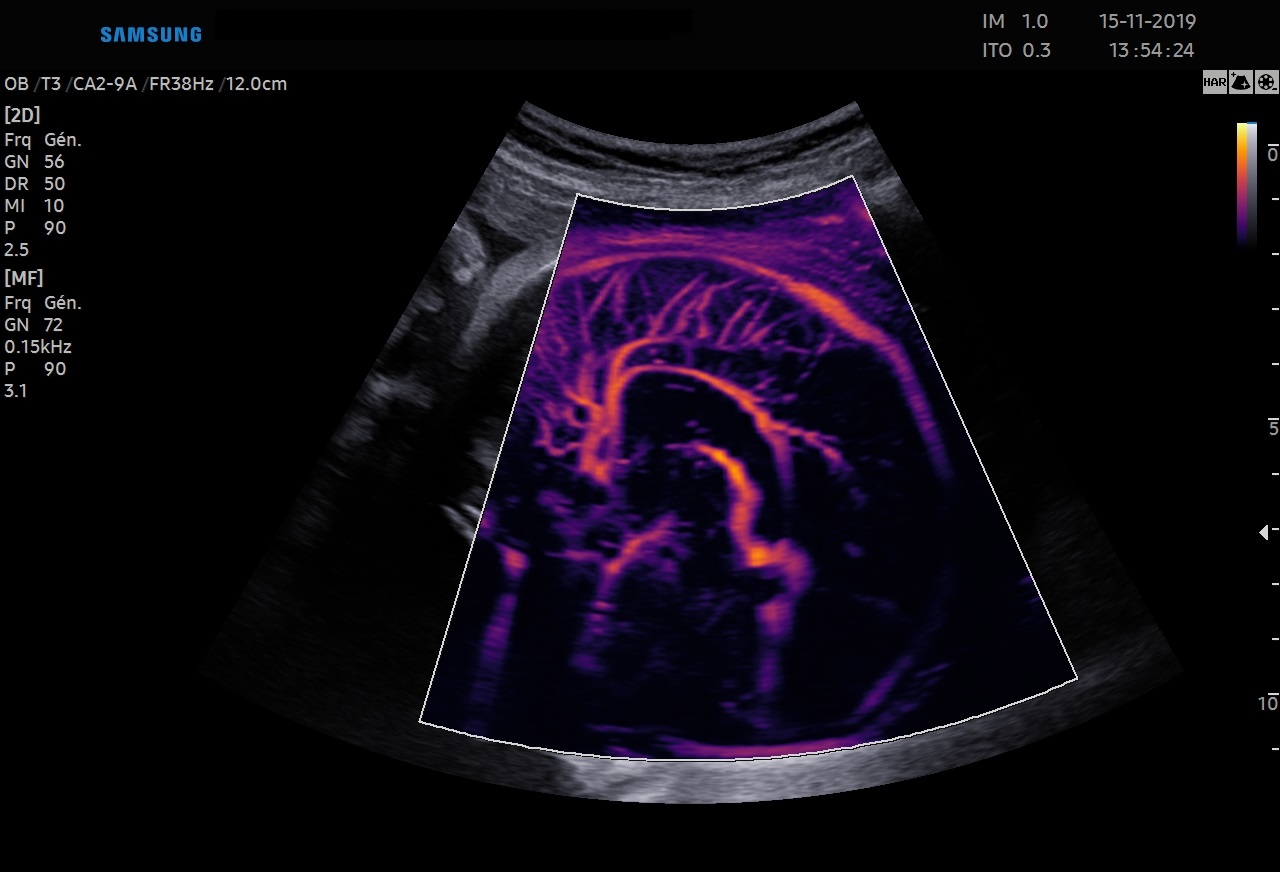

Le MV-Flow™ offre une nouvelle alternative au Doppler Énergie pour visualiser les flux lents et la microvascularisation des structures. Les hautes cadences images et les filtres d’imagerie avancés permettent au MV-Flow™ de coder le mouvement des hématies en s’abstenant des artefacts de l’imagerie B et ainsi améliorer la résolution spatiale.